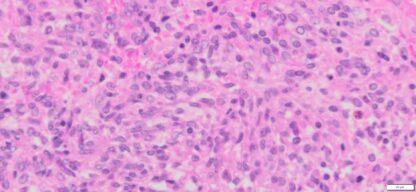

Description

| Organ& Tissue | Pathology Diagnosis | Gender/Age | % Tumor Area | Grade | TMN Stage | IHC Data |

| Human liver | Liver metastases from human gastric stromal tumor | Male/54 | 45% | II | pT4pNxpM1 | NA |

Human tissue was fixed in formalin immediately after excision and embedded in paraffin. The tissue sections were 5 µm in thickness and mounted each on positively charged glass slides.